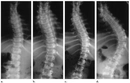

Skolyozun tanısı genellikle fizik muayene ve görüntüleme yöntemleri ile konulur.

• Fizik muayene sırasında doktor, omurganın görünümünü değerlendirir ve belirtileri inceler.

• X-ray, skolyozun derecesini belirlemek için en yaygın kullanılan görüntüleme yöntemidir.

• Gerekirse, MRI veya CT taramaları ile daha detaylı bilgi edinilebilir.

Bu yöntemler, skolyozun ciddiyetini ve tedavi gereksinimlerini belirlemede kritik öneme sahiptir.